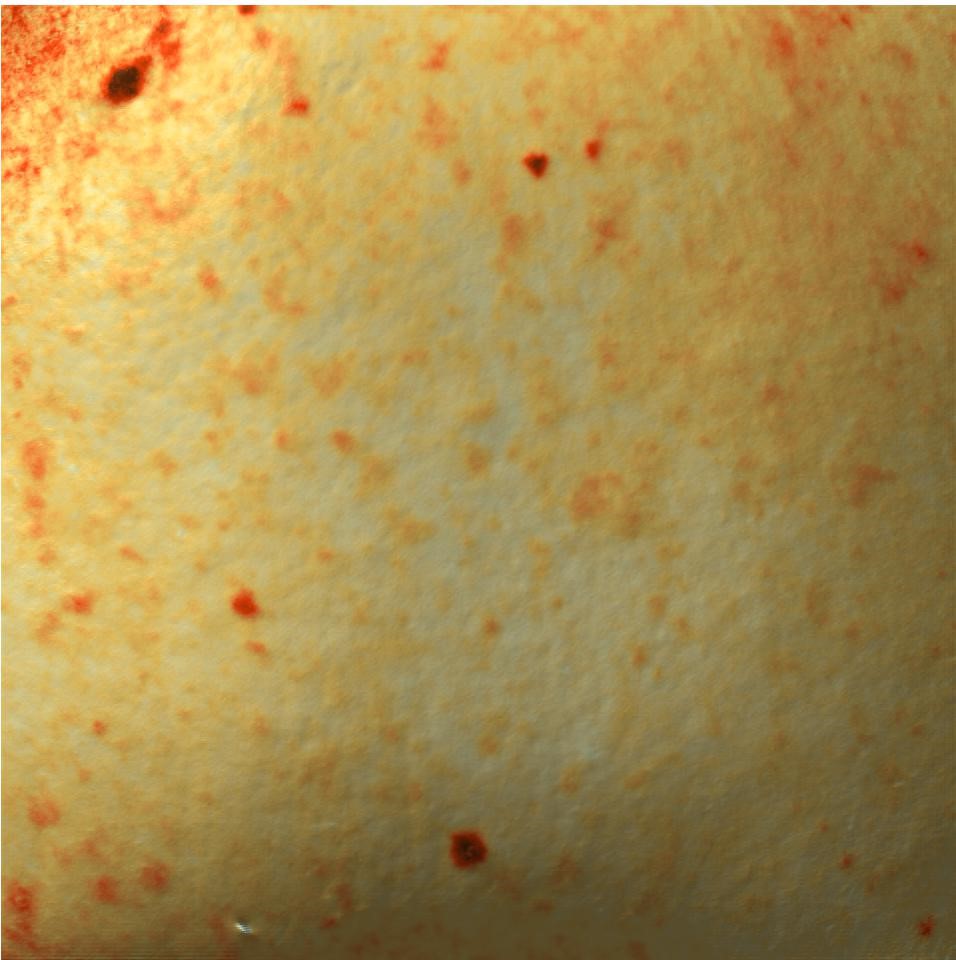

Также для фотодокументации клинических результатов был применен аппарат трехмерной визуализации поверхности кожи Antera 3D. Он предназначен для оценки состояния сосудистого компонента, интенсивности гиперпигментации, глубины залегания морщин различного калибра, ширины и количества пор, а также рельефа тканей. В данном исследовании использовалось документирование в режиме «меланин».

Монотерапия проводилась на аппарате IPL Venus Versa. Комбинированная терапия включала в себя проведение терапии IPL Venus Versa, а также препарат Bellarti Hydrate, в состав которого входит натрия гиалуронат и маннитол 0,49 мг.